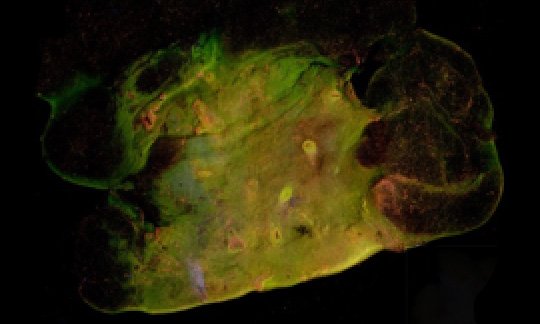

Breast tumor margin imaging sampleIn March of 2018, Dr. Yu’s new breast tumor margin imaging team submitted a Marquette University College of Engineering GHR grant to fund work on the MUSE-based device, which the team named the Deep UV fluorescence scanning microscope, or DUV-FSM.  Dr. Yu coordinated with Mollie Patton and Mary Rau from the MCW Tissue bank to acquire discarded breast tissues, and Dr. Julie Jorns, a pathologist from MCW, joined the team, lending her expertise to reading imaged tissue samples, ensuring that the tested medium was correctly distinguishing between cancerous and non-cancerous cells. Finally, in the fall of 2018, Dr. Dong Hye Ye, a deep learning specialist from Marquette University, came on board to facilitate image analysis.  With Dr. Ye’s arrival, Dr. Yu’s breast tumor margin imaging team was complete.

By early 2019, the initial phases of the project had begun to yield results. The DUV-FSM system was fully ready for tissue imaging. Tongtong had spent several months working with Dr. Gilat-Schmidt to ensure that the use of contrast medium had been optimized for their objectives. The study using discarded human breast tissues from the MCW Tissue Bank had been approved by the MCW IRB, and the first ten fresh surgical samples imaged using the team’s developing technology showed excellent visual contrast in color, tissue texture, cell density and shape between invasive carcinomas and their normal counterparts.

By early 2020, over 50 breast tissue samples had been imaged by the DUV-FSM, and corresponding Hematoxylin and Eosin (H&E) images had been collected by Dr. Jorns. The images had been visually evaluated by a group of non-medical researchers, with accurate distinction between cancerous and non-cancerous cells at a sensitivity and specificity of 96 and 92%, respectively. Objective diagnosis using nuclear-cytoplasm ratio (N/C) calculated for each 2 mm x 2 mm patch was able to differentiate patch-level invasive carcinoma from normal breast tissues with reasonable sensitivity (81.5%) and specificity (78.5%), numbers the team were confident would increase even further with the eventual implementation of Dr. Ye’s deep-learning methodology.

When asked why he believed the project was chosen for the cover, Dr. Yu responded with the following: “Our approach is simple, and it generates wonderful visual contrast.”  He went on to add, “The editor of the Journal of Biomedical Optics is an expert on margin assessment. I am sure he is the person who chose our study for the cover page. He said he was very excited about our study, that we have done terrific work, and that the images are stunning.”